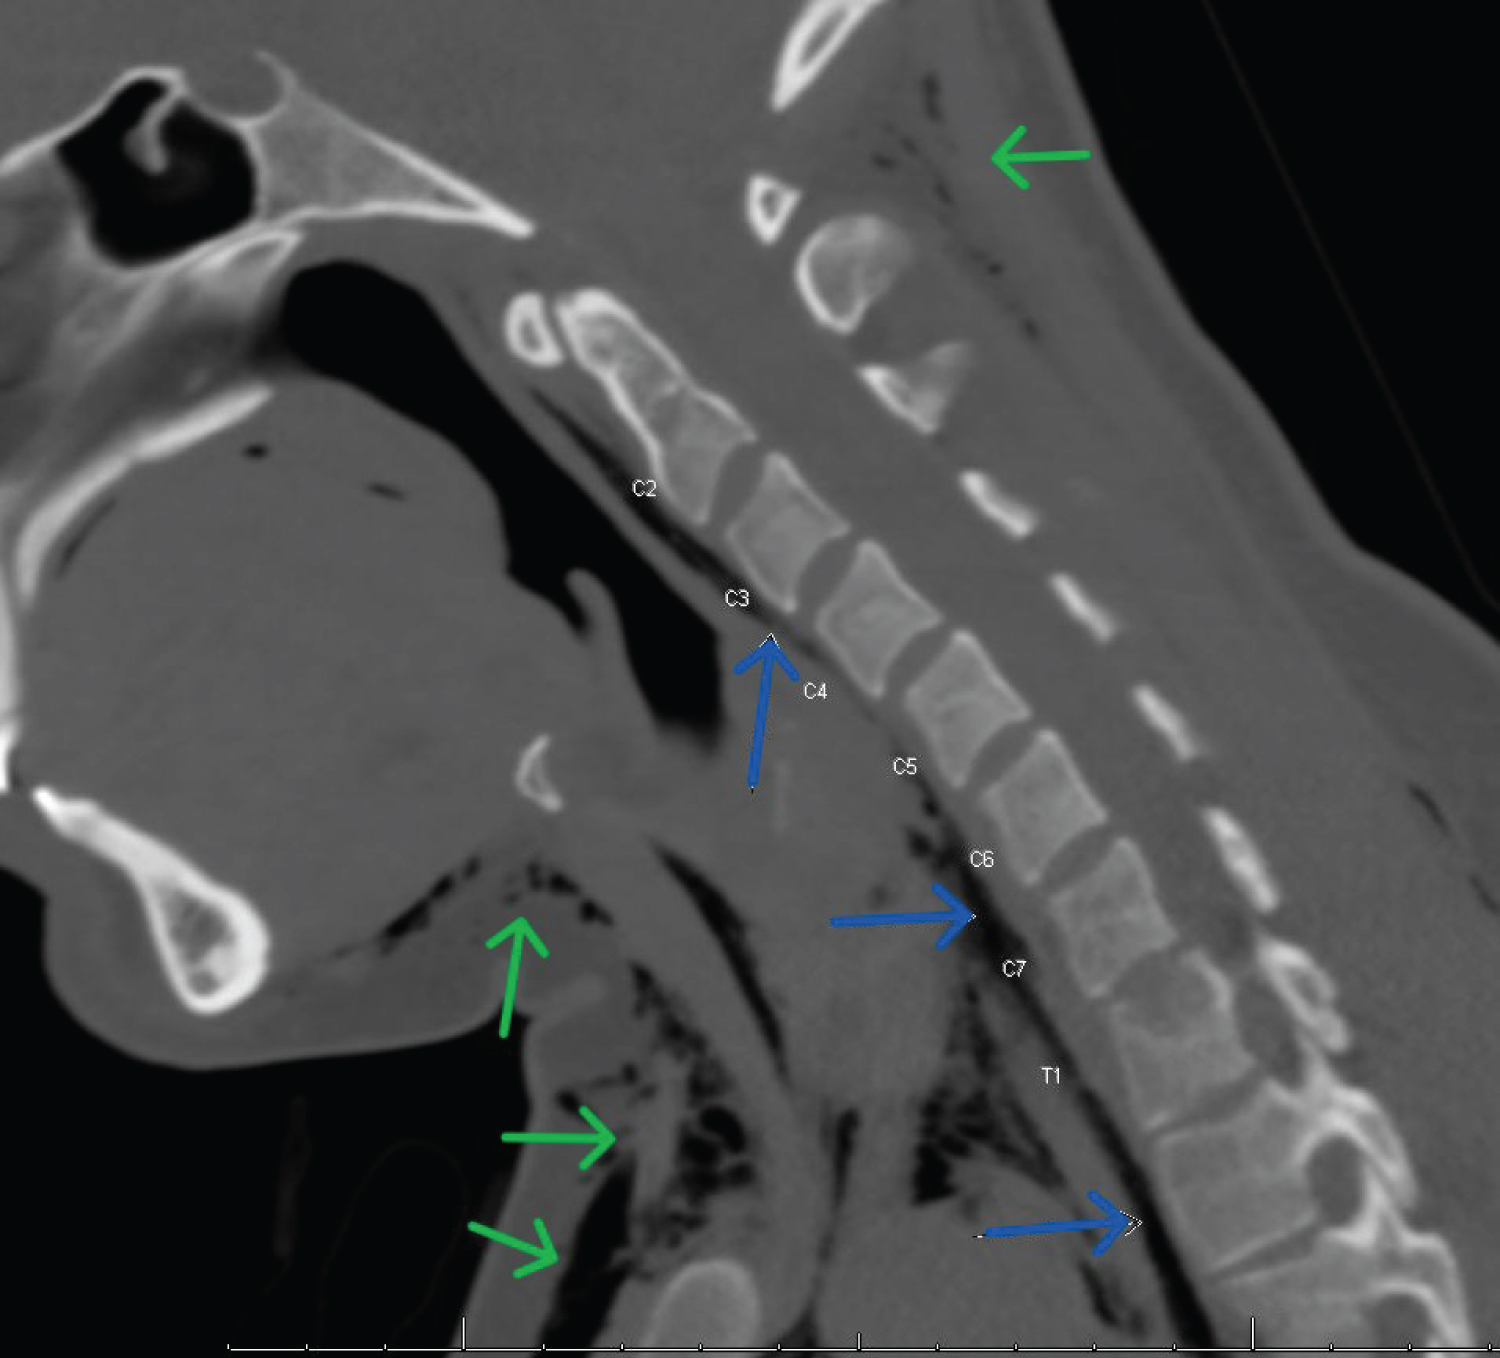

CT head and neck soft tissue without contrast showed extensive pneumomediastinum with lateral extension into bilateral extra-pleural spaces and extensive subcutaneous emphysema involving the chest wall, neck, face, right temporal, and bilateral occipital scalp. The neck subcutaneous emphysema extended medially to involve the right C5-C6 to C7-T1 neural foramen and right epidural space (Figure 2). No obvious airway or cervical esophageal injury was identified.

Figure 2: CT neck without contrast, sagittal slice. Blue arrows indicate extensive pneumomediastinum intimate with vertebral bodies and neural foramina. Green arrows indicate subcutaneous emphysema along the anterior chest wall and occiput. View Figure 2